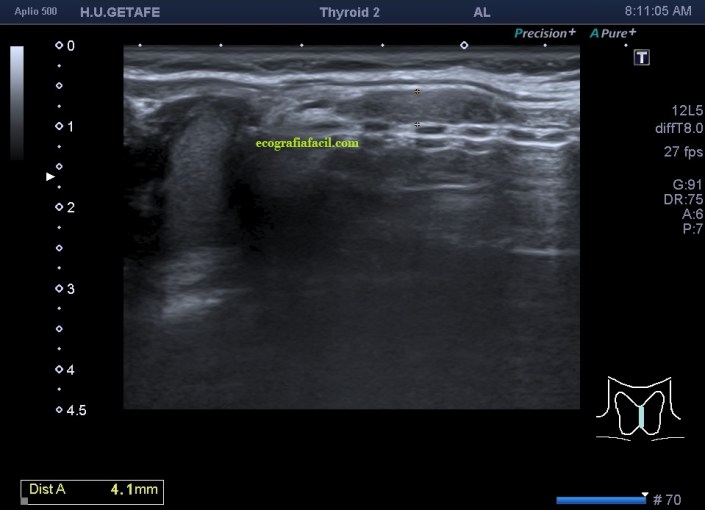

Era un nódulo hiperecogénico en el contexto de la tiroiditis en el estudio de una ecografía tiroidea.

Te enseño las imágenes, típicas de una exploración tiroidea de protocolo con semiología de tiroiditis.

Mira las imágenes y luego te explico un poco, poco, porque no tiene mucho que explicar…

De la imagen 1 a 7 el protocolo habitual, el estudio particular del nódulo con medidas y aplicación del doppler demuestra el aspecto típico del Caballero Blanco.

Resumen de las imágenes que has visto en el caso de hoy:

- Hipoecogenicidad del parénquima

- Heteroecogenicidad

- Múltiples nódulos hipoecoicos muy pequeños